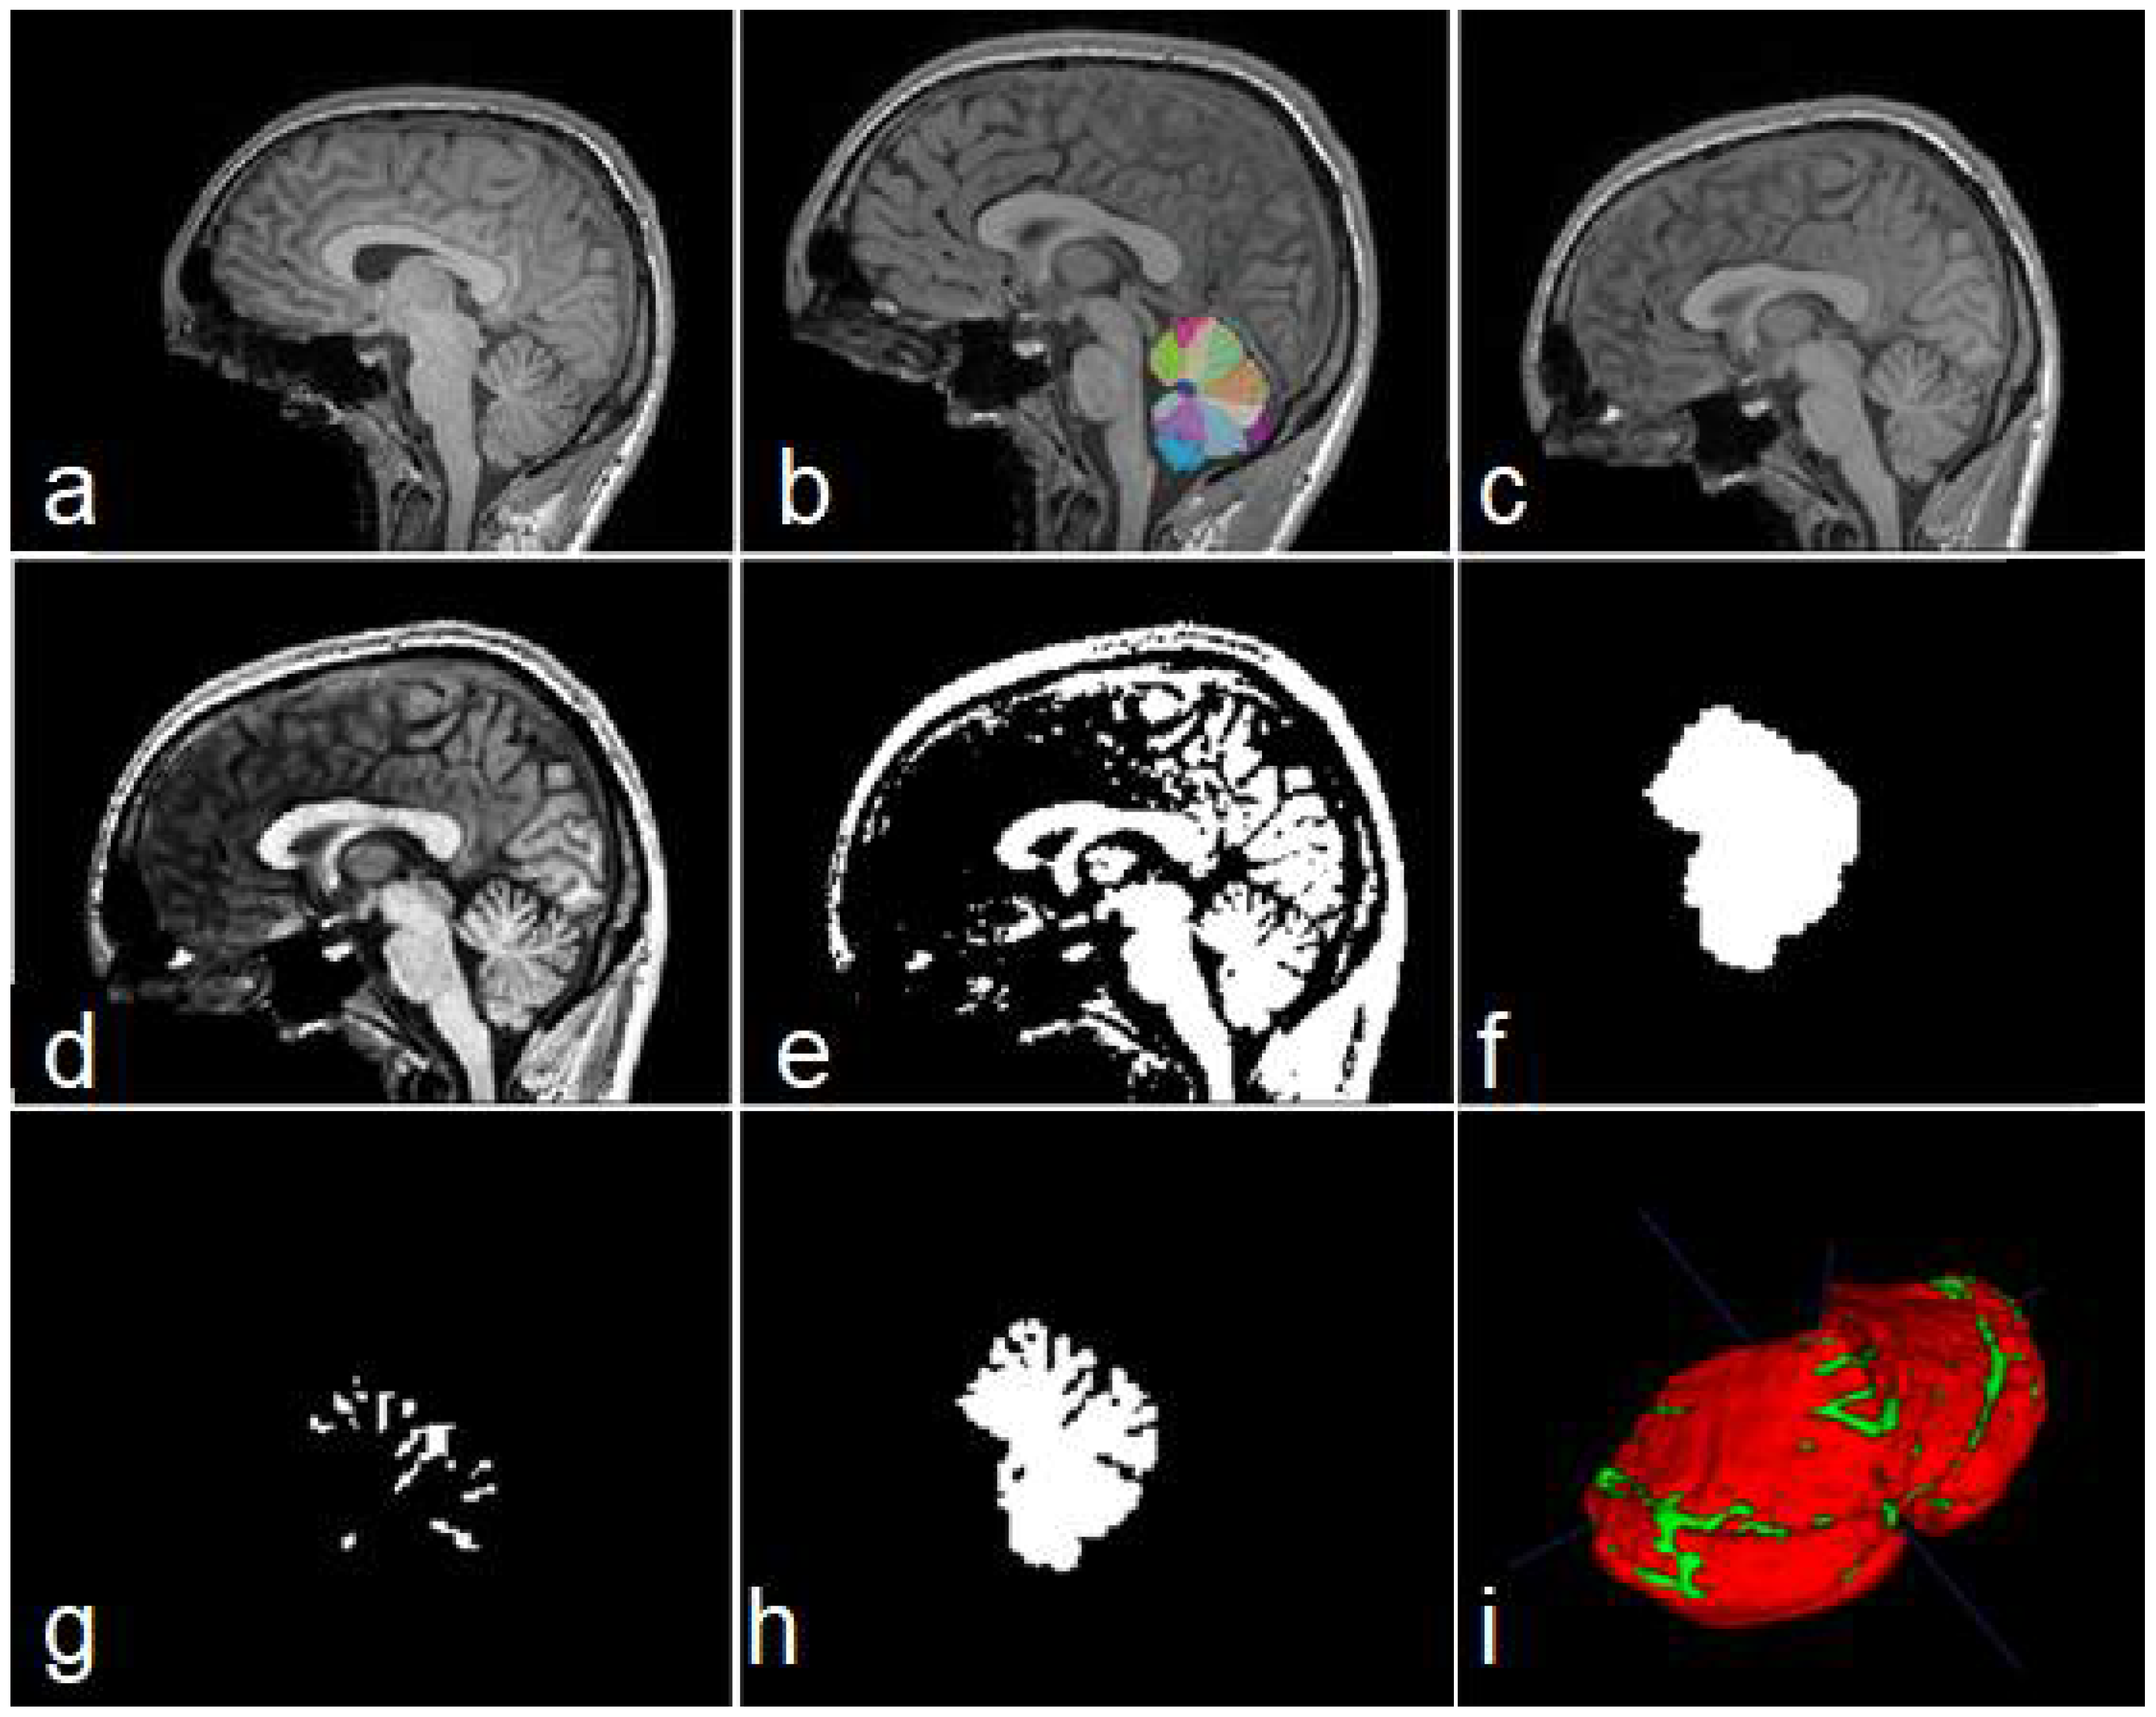

Figure 3.

Steps of data construction procedure. Sagittal views of the original image (a), cerebellar mask obtained with ACAPULCO (b), result of BFC and registration (c), contrast-enhanced image (d), binary image obtained (e), feature map containing the whole cerebellar tissue (f), obtained fissures mask (g), and cerebellum with fissures (h). In (i) a 3D view of the union of (g,h); red color represents the cerebellar tissue, and green color shows the fissures.

Building a manually labelled dataset from 3D images is a very difficult task. For this reason, we created a simple procedure for the preparation of our dataset. For each MRI, the following steps were applied:

- Obtain a cerebellar mask, using any existent technique. See Figure 3b.

- Bias Field Correction (BFC) for reducing intensity inhomogeneities. The algorithm used in this research was the N4 method [32].

- Image registration to the 1 mm isotropic ICBM 2009c template [33] in MNI space. See Figure 3c.

- Obtain a contrast-enhanced image (Figure 3d).

- Binarize equalized image using any existent technique (Figure 3e).

- Build a mask containing the cerebellar segmentation obtained in step 1 (output 1). See Figure 3f.

- Build a feature map containing cerebellar fissures, by applying binary xor operation to outputs from steps 5 and 6 (output 2, Figure 3g,i).

- Build a feature map containing the cerebellar tissue, with all its fissures, by subtracting output 1 from output 2 (output 3, Figure 3h,i).

- Imaging cropping for reducing computational cost.